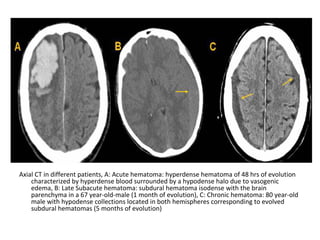

5-Mass Effect :